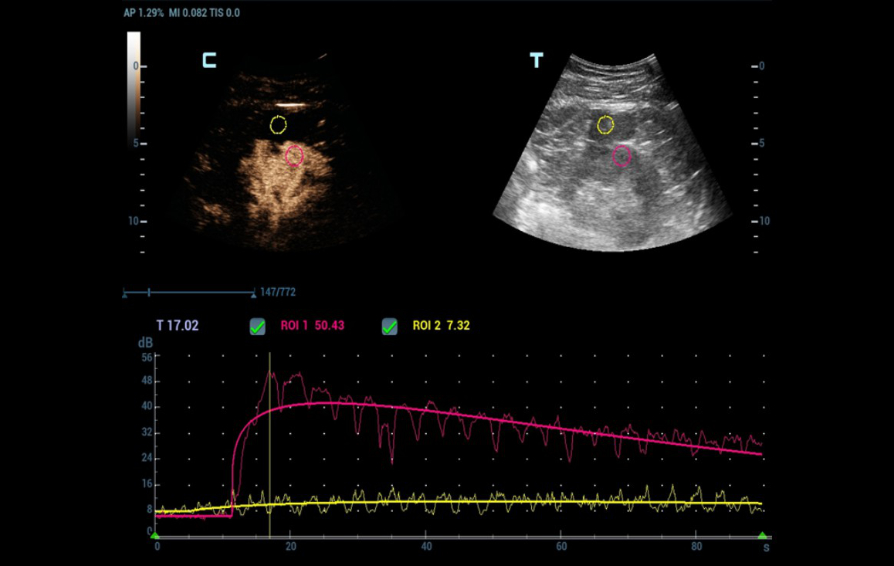

2) Contrast Enhanced Ultrasound (CEUS)

As Power Doppler showed indeterminate results regarding internal flow within the complex cystic mass, CEUS was performed through injection 1.2 ml of Sonovue (Bracco Swiss, SA, Switzerland). The longitudinal plane of the kidney with the maximum section of the cystic mass was selected for scanning. At the end, the cystic mass was characterized as benign by a lack of enhancement throughout the CEUS study (Figure 4 and 5).

Quantitative analysis also confirmed the absence of enhancement within the cystic mass (Figure 6).